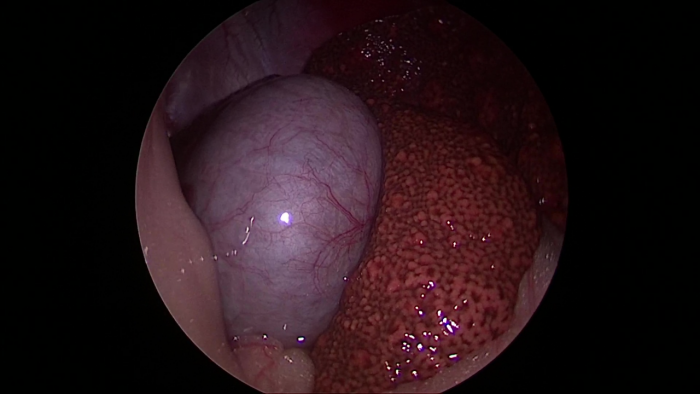

この写真ってなにか分かりますか?

実はこれは腹腔鏡で見た胆嚢と肝臓なんです。

動物医療センター・ALOHAやあそう動物病院では、この肝生検の検査にも腹腔鏡を使います。通常だと少なくても10cmはおなかをあけないとできない検査が、5〜10mmの小さな穴を1〜2カ所開けるだけで、この写真の様におなかの中を観察でき、肝臓の一部を取ってきて検査する事ができます。胆嚢の状態や肝臓の見た目の状態も手に取るように分かります。